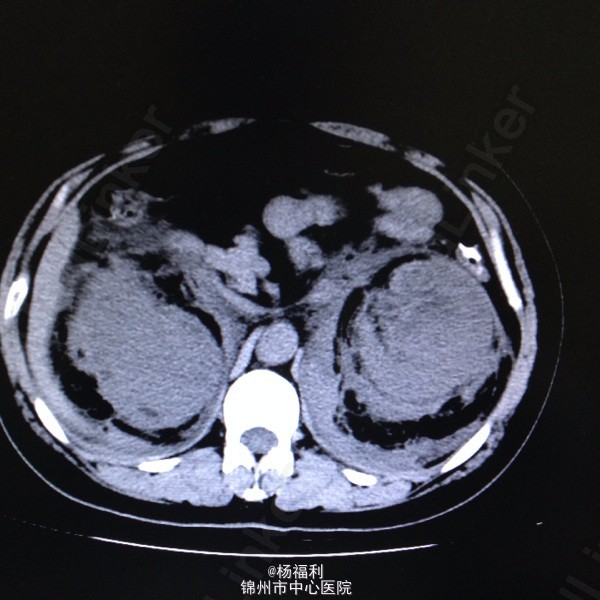

44岁女患。为消化科我会诊患者。 现病史:以上腹痛9小时为主诉入院。无发热及寒战、噁心未呕吐,无腹泻及黑便。 既往史:双眶炎性假瘤2年,口服激素治疗,并补钾。

查体:上腹部压痛,无反跳痛、右侧压痛明显,右肾区叩击痛,左肾区轻叩击痛,双输尿管走形区无压痛。 辅助检查;泌尿系彩超:双肾积水。 血白细胞:9.99*10^9。 肾功能正常。 全腹部ct及MRU检查:见图片。

诊断;真的不知道是啥病。 处理:暂时止痛处理。双肾病变。不知从哪里下手。